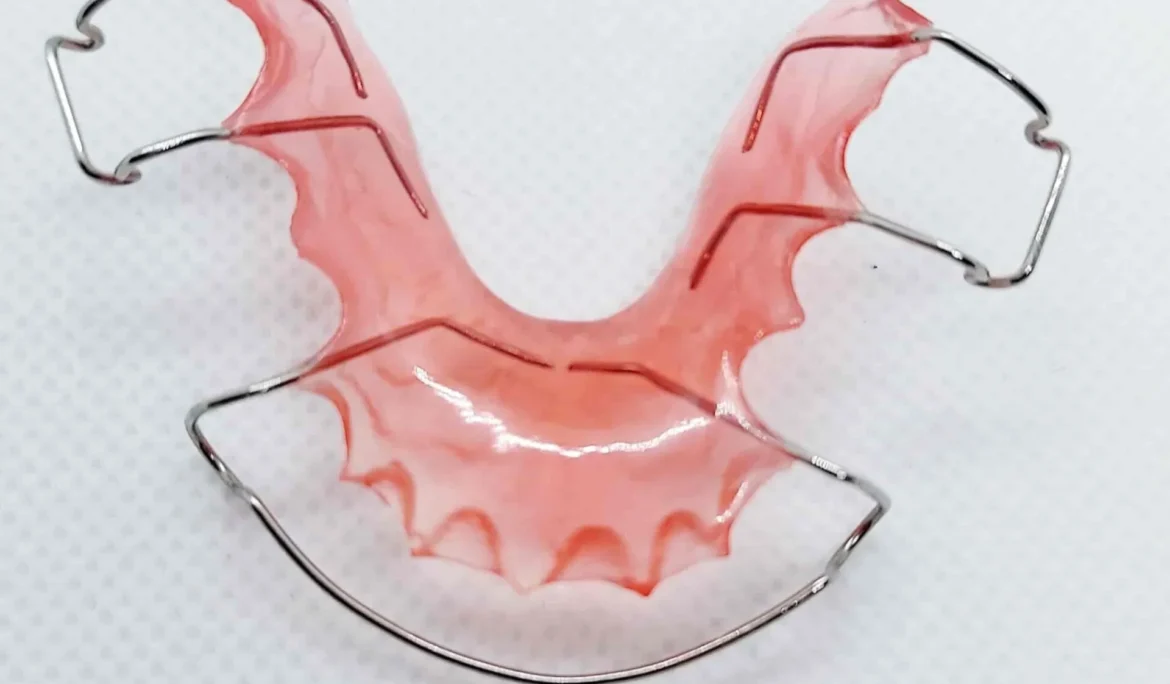

Hàm duy trì là một loại khí cụ bắt buộc phải sử dụng khi bạn đã hoàn tất quá trình niềng răng. Nếu không đeo hàm duy